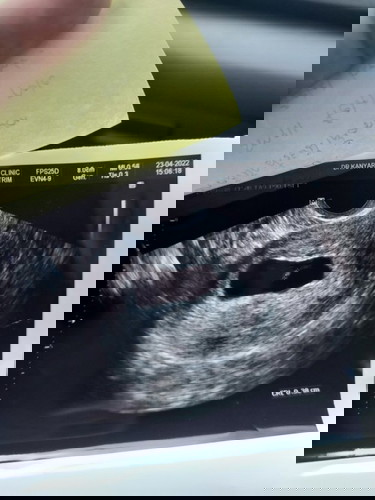

กอดหน่อยค่ะ เราพึ่งผ่านมาได้1วันที่น้องหลุดออกเอง เศร้าเหมือนค่ะพึ่งแท้งครั้งแรกแต่เป็นท้อง2 แม่มีลูกมาแล้ว1คน วัยกำลังซน2ขวบ ตอนแรกก็ทำตัวไม่ถูกเพราะไม่เคยแท้ง แอบนอยเศร้าว่าทำไมเพราะน้องมีหัวใจเต้นแล้วแต่กลับหยุดเต้นไปเฉยๆ ความรุ้สึกไม่รู้จะอธิบายยังเลยค่ะ แต่ดีที่มีลูกคนโต ค่อยอยุ่ด้วยเห็นเค้ายิ้มหัวเราะก็กานเศร้าไปได้หน่อยค่ะ เพราะเราต้องเดินหน้าต่อไปค่ะ เป็นกำลังใจให้นะค่ะ สู้ๆค่ะ

สู้ๆนะคะแม่ บ้านนี้อัตราซาวเจอแค่ตัวน้องยังไม่เจอหัวใจน้องเลยค่ะ ตอนนี้ก็กลัวมากๆเลยค่ะ ได้แต่ภาวนาค่ะ 🥹✌️